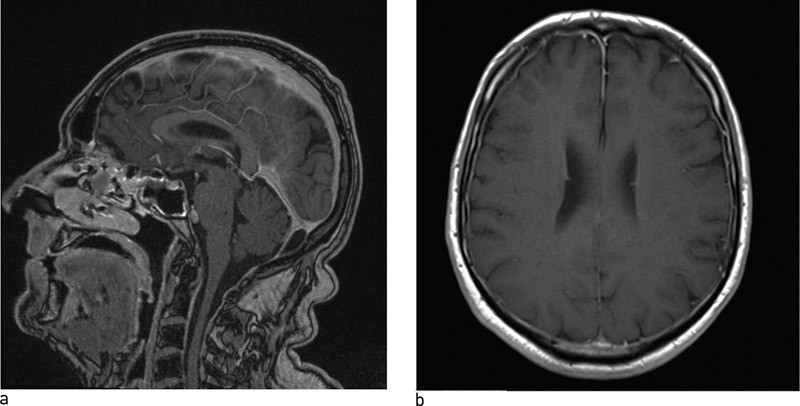

Ved lavtrykkshodepine, inklusive postdurapunksjonshodepine, vil MR caput gjerne vise diffus kontrastoppladning i pachymeninges (fig 2) og redusert ventrikkelstørrelse, ev. at cerebellare tonsiller strekker seg ned i foramen magnum, at basale cisterner er avflatet eller utslettet eller at hypofysen er forstørret (11). Ved tvil kan CT myelografi, cisternografi eller spinal MR med tynne snitt kunne avdekke hvor cerebrospinalvæskelekkasjen sitter (38).